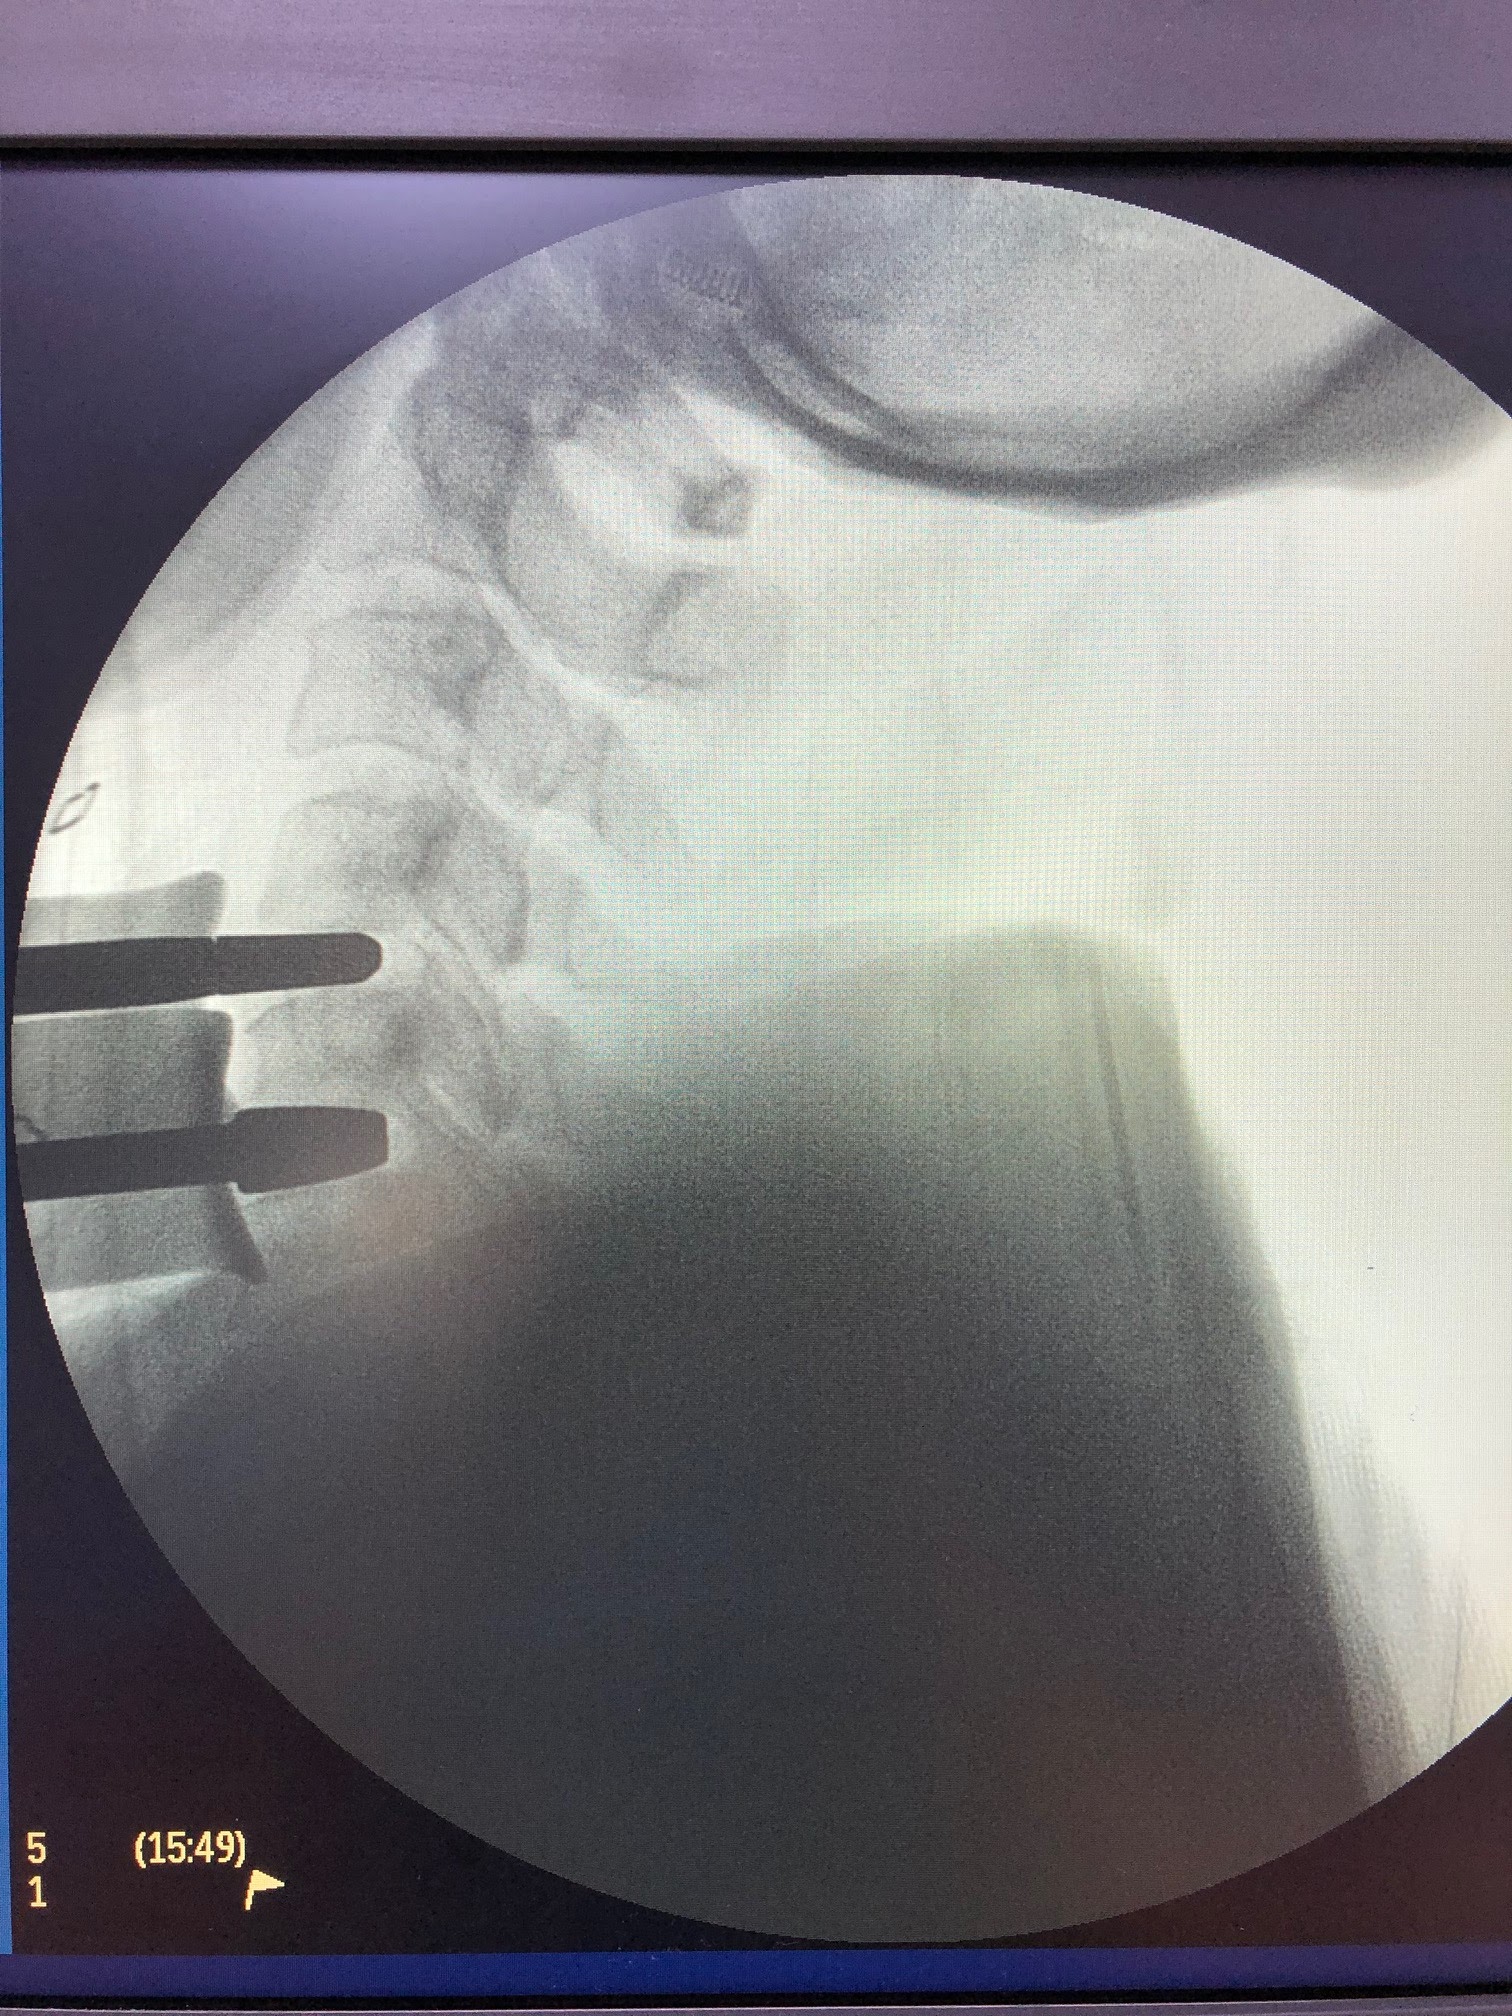

360 degrees decompression of spine

Our Spine Surgery Team of Dharamshila Narayana Superspeciality Hospital, Delhi-96, comprises of Dr. V.A.Senthil Kumar, Spine Surgeon and Dr. Ashish Kumar Shrivastav Neurosurgeon. We, recently performed a 360 degree Decompression of Cervical spine ( Combined Anterior ACDF and posterior Decompression -laminectomy), in a single sitting. The patient was a 42 year old lady from Bareilly with severe spastic UMN lesion due to PIVD C4/5 and C5/6 with LFH with global cord compression at these levels. She reported subjective improvement and walked the very next day.